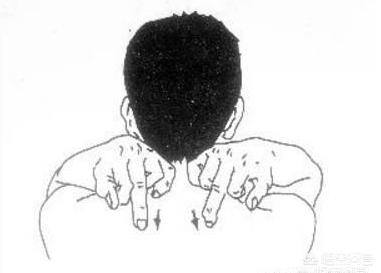

3. une action bénéfique pour les poumons

taper sur les poumons autour de la tempe (idiome) ; fig. frapper sur les points d'acupuncture des poumonsChaque soir avant de se coucher, assis sur une chaise, les deux genoux naturellement séparés, les mains sur les cuisses, la tête fermée, tout le corps détendu, l'intention de garder le dantian.

Inspirer dans la poitrine, les deux mains serrées en un poing creux, frapper l'arrière du point Lung Yu (position à l'arrière de la troisième vertèbre thoracique sous l'apophyse épineuse, à gauche et à droite à côté de l'ouverture de la largeur de deux doigts) des dizaines de fois, et en même temps lever la main avec la paume des deux côtés de l'arrière du bas vers le haut du tapotement léger, pendant environ 10 minutes.

Cette méthode permet de détendre le qi dans la poitrine, d'avoir un effet sur la santé des poumons, d'aider le corps à évacuer les mucosités et de passer par le méridien de la colonne vertébrale pour prévenir les rhumes.